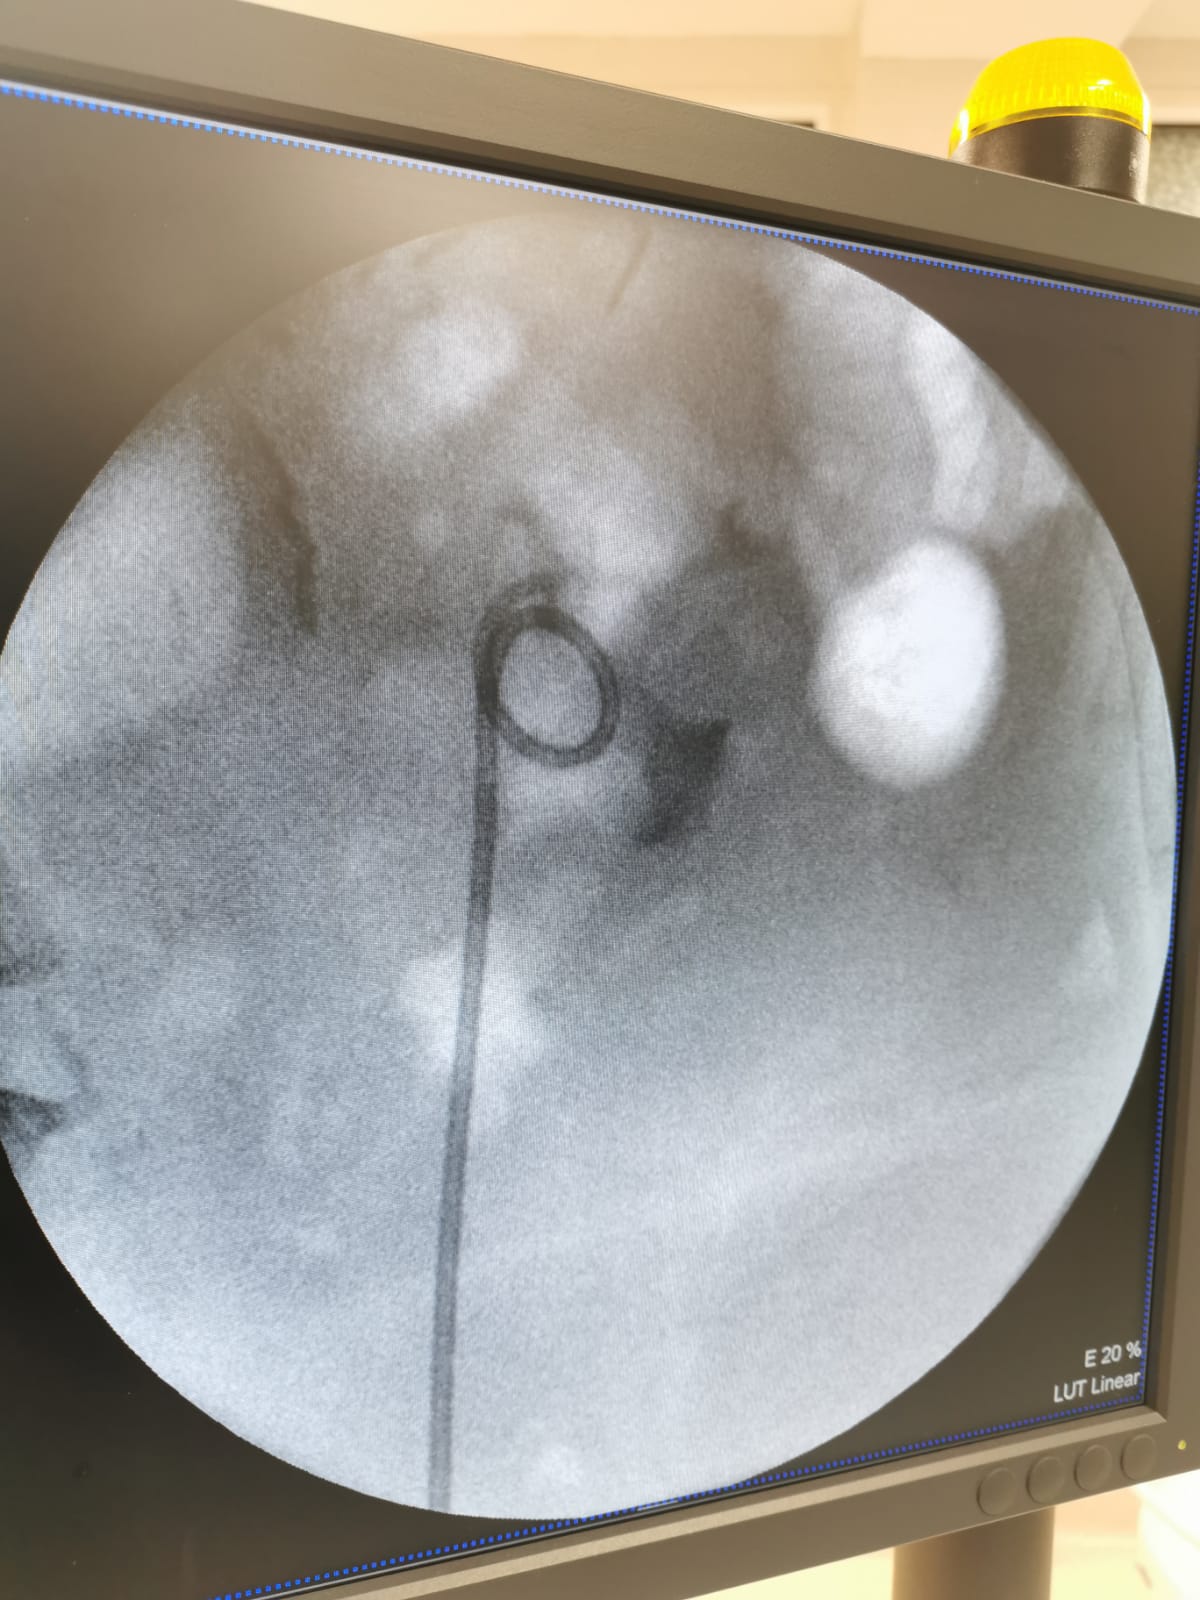

Citește mai multUreterorenoscopia

Ureterorenoscopia Despre… Reprezintă intervenţia chirurgicală endoscopică ce permite atât vizualizarea ureterului şi a căilor urinare [...]